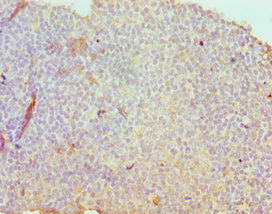

Immunohistochemistry of paraffin-embedded human tonsil tissue using CSB-PA020888ESR2HU at dilution of 1:100